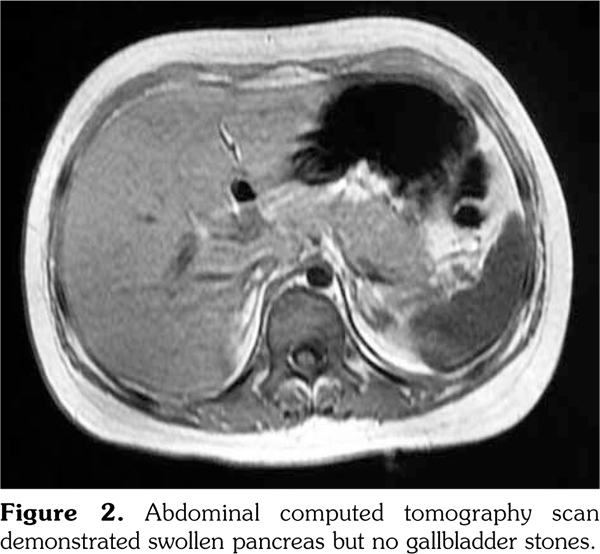

An 11-year-old girl was admitted to our department with a six-month history of anorexia and rashes on her face and extremities (Figure 1). On admission, her axillary temperature was 37.7°C, heart rate was 130 beats/minute, blood pressure was 82/47 mmHg, respiratory rate was 22 breaths/minute, and oxygen saturation was 95%. Cardiac examination revealed a soft systolic murmur at the apex with low heart sounds. She had malar rash, discoid rash, hepatosplenomegaly, and edema of the lower extremities. The subsequent autoimmune and serologic workup came back positive for anti- nuclear antibody at a titer of 1:3200, positive anti- double stranded deoxyribonucleic acid, anti-Smith antibody, and low complements (0.28 g/L) and complement 4 (C4) (0.03 g/L). Other laboratory studies exhibited anemia (red blood cell 3.1∞1012/L, hemoglobin 99 g/L), proteinuria (24-hour urine protein 300 mg/day), elevation of acute-phase reactants (C-reactive protein 132 mg/L, erythrocyte sedimentation rate 54 mm/hour), hyperamylasemia (208 units/L), hyperlipasemia (1556 units/L), and raised creatine kinase (CK, 375 units/L) and CK-MB (83 units/L). Electrocardiogram revealed sinus tachycardia with T wave inversion. Echocardiography showed normal left ventricular size but global hypokinesia with an ejection fraction of 37%. Abdominal computed tomography demonstrated swollen pancreas but no gallbladder stones (Figure 2). Renal biopsy revealed diffuse proliferative glomerulonephritis Class IV-G. Our patient was diagnosed as having systemic lupus erythematous (SLE) complicated by pancreatitis and myocarditis. SLE disease activity index score was 24. She was treated with a course of pulse methylprednisolone 10 mg/kg/day for three days and subsequently converted to oral prednisone (60 mg/day). In addition, several symptomatic treatments such as bowel rest, nutritional support, somatostatin, and fructose-1,6-diphosphate were also adopted. One month later, intravenous cyclophosphamide 500 mg/m(2) was given. Two months later, repeated echocardiography showed a marked improvement in ejection fraction, abdominal computed tomography revealed a less swollen pancreas, and SLE disease activity index score was 2. The patient was discharged with normal pancreatic (amylase 109 units/L, lipase 285 units/L) and myocardial enzymes (CK 29 units/L, CK-MB 11 units/L).

Myocarditis is an uncommon feature of SLE, and its clinical manifestations are variable, ranging from asymptomatic presentation to cardiogenic shock. In the present report, our patient was diagnosed with myocarditis on the basis of hypotension, cardiac auscultation, diffuse T-wave inversion on electrocardiogram, elevated cardiac markers, and echocardiographic findings. Particularly, the presence of global hypokinesia with a low ejection fraction on echocardiography is strong evidence towards the diagnosis.(3) However, myocardial biopsy is used infrequently because of perceived risks and the low specificity of the histology. Besides myocarditis, SLE in this case was also complicated by pancreatitis, according to elevation of pancreatic enzymes and characteristic imaging findings. Although the exact mechanism has not been revealed yet, the pathogenesis of SLE-associated pancreatitis may include vasculitis, hemolysis, micro- thrombus formation, anti-pancreatic antibodies, and inflammation due to T-cell infiltration and complement activation.(4)